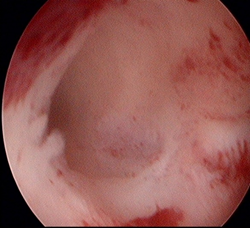

术后正常的宫腔

腹腔镜下看见子宫的宫底形似马鞍,双侧输卵管和卵巢粘连的一塌糊涂。宫腔镜下看两个阴道,两个宫颈 ,两个子宫。